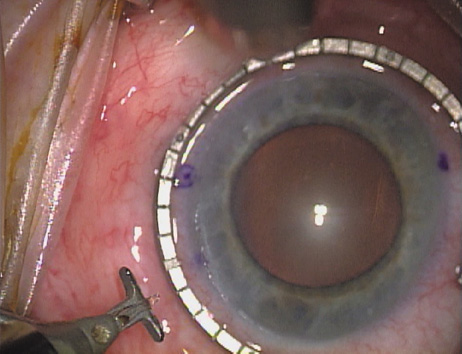

Case 2 is a 79-year-old woman who presented with a very dense left cataract. Her refraction was recorded at −2.25 +2.75 × 125 with a difficult end point. Her manual keratometry and topography measurements were consistent and revealed slightly less than 1.75 D at 120 degrees. Because of the questionable refraction, greater value was placed on the corneal measurements. Based upon the cataract nomogram, the plan was for paired LRIs of 40 degrees to be placed over the steep 120-degree axis (Figs. 1219).

Fig. 12. In this left eye, the steep meridian is at the 120-degree axis and has been delineated by opposing limbal marks. The upper left hand ink mark represents the 6:00 position for orientation. (Reprinted from Hardten DR, Lindstrom RL, Davis EA. Phakic Intraocular Lenses: Principles and Practice. Thorofare, NJ: SLACK Incorporated, 2004, with permission.)